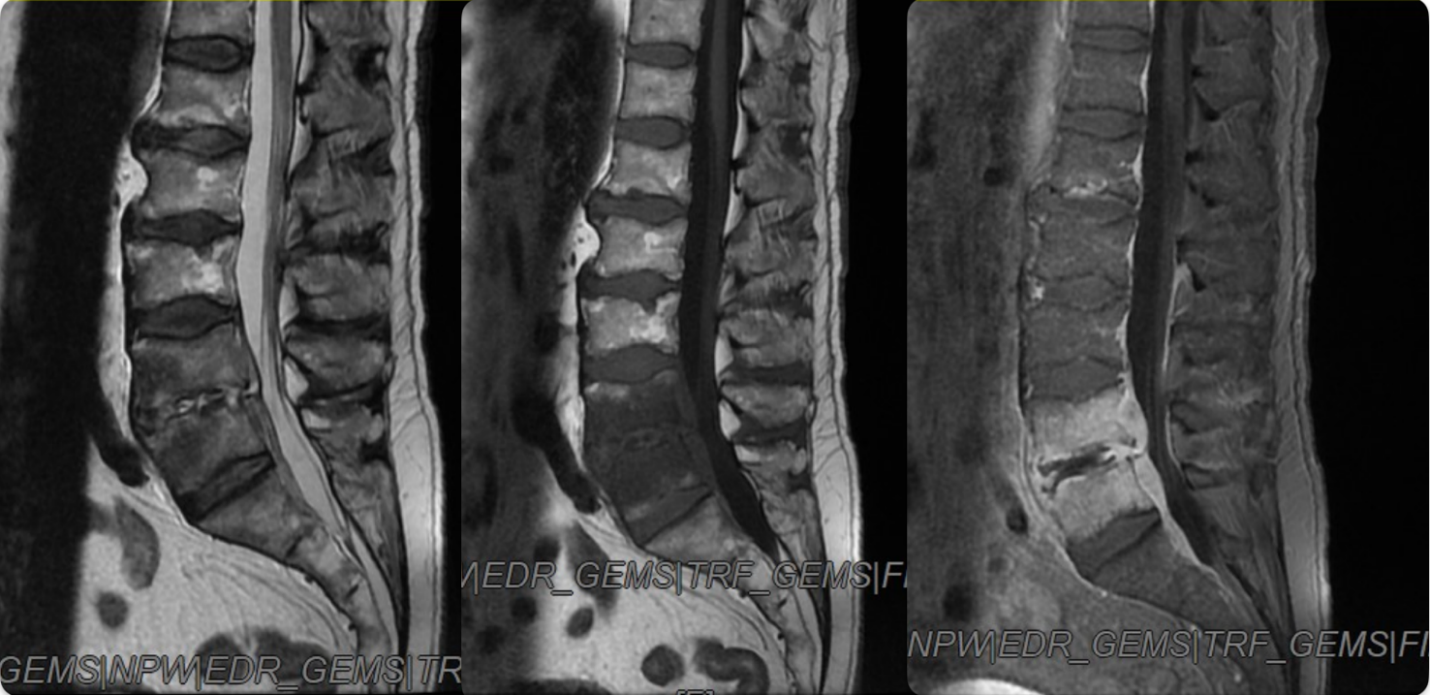

We took another full spine MRI, this time using iv contrast, exactly one week later the first outpatient MRI, which showed an unexpected decrease in size of the entire SEA (Figure.2)

Especially, the posterior L2-L3 collection appeared barely visible in the new study.

Figure 2: A. MRI T2 sequence, no iv contrast- Decrease in size of both the epidural collection, especially the posterior one.

B. MRI after iv contrast-enhancement of the two small anterior and posterior epidural collections. Increased high signal of vertebral plates

After three weeks from the first MRI taken in our hospital and two weeks from the beginning of the antibiotic therapy, another MRI with iv contrast was performed and displayed a further slight reduction of the abscess, but a greater involvement of intervertebral discs and endplates, as predictable as a spondylodiscitis (Figure. 3).

Figure 3: A. MRI T2 sequence, no iv contrast- minimal hyperintense signal in the upper side of the previous posterior epidural collection at L2-L3 level and anterior epidural collection L3.

B. MRI T1 sequence, no iv contrast- minimal hypointense signal of anterior epidural collection at L3 and L4 level.

C. MRI After contrast- No signs of the posterior epidural collection, enhancement of the anterior epidural collection, increased high signal of L4 and L5 vertebral bodies At this point we could switch the iv-antibiotic therapy to an oral one with doxycycline and levofloxacin, following specialist recommendation, and discharge the patient scheduling radiological and clinical controls.